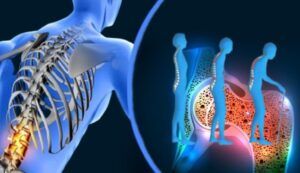

Alimente și băuturi care îți macină oasele. La fel ca în cazul multor alte afecţiuni, alimentele pe care le alegem pentru consum pot juca un rol important în prevenirea sau controlul afecţiunilor.

Mai jos veţi găsi o listă cu alimente care pot afecta oasele, însă nu toată lumea trebuie să renunţe definitiv la ele, ci în special cei care ştiu că prezintă un risc de dezvoltarea a afecţiunilor musculo-scheletice, precum indivizii care au în familie cazuri de osteoporoză.

Iată câteva dintre alimentele ce afectează sănătatea oaselor şi pe care, cel puţin, unii dintre noi ar trebui să le evite.